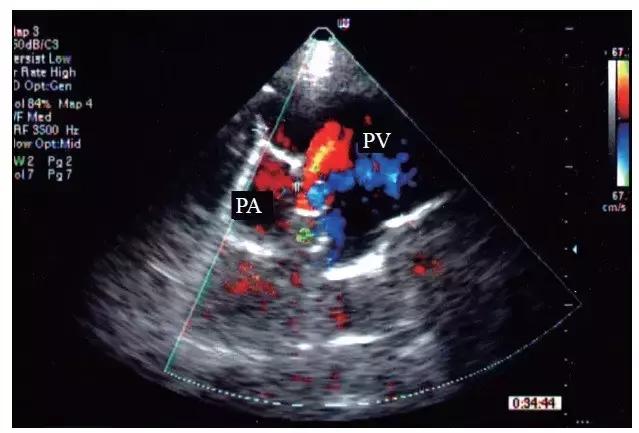

5.在闻及连续性杂音的部位探查,往往可显示肺动脉内五彩镶嵌血流射入呈瘤样扩张的肺静脉内(图1),连续多普勒在瘘口处取样为连续性湍流频谱(图 2)。

图1 肺动静脉瘘的彩色多普勒表现